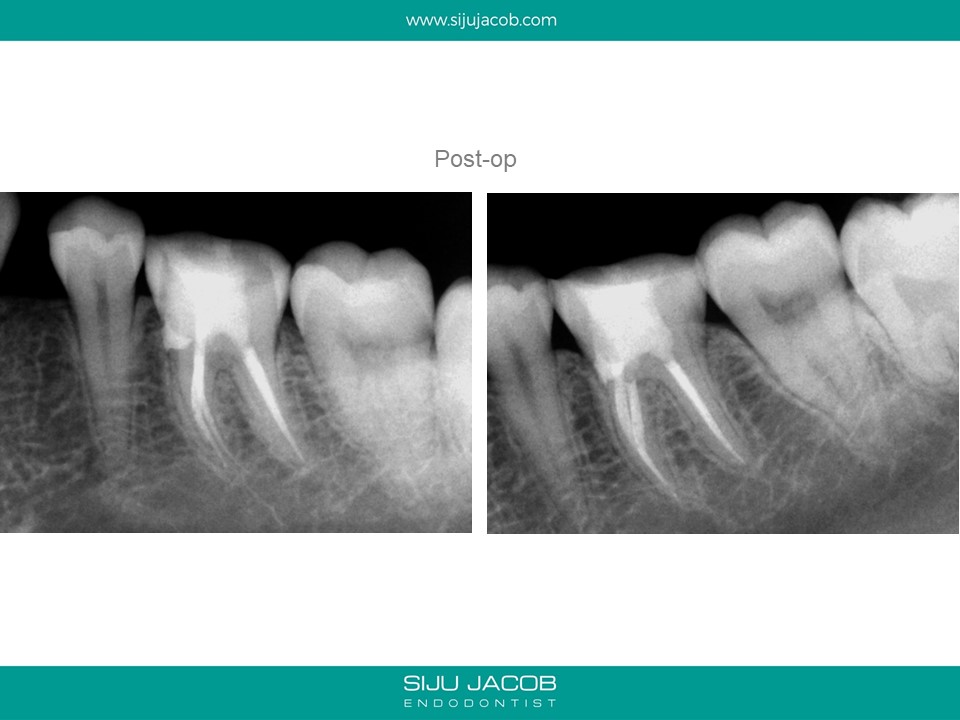

Whenever I get a case started by someone else, I warn the patient about the fact that I’m not really sure what the previous practitioner has done. Most times, the damage isn’t that bad. Occassionally, we get surprises like this one: A perforation.